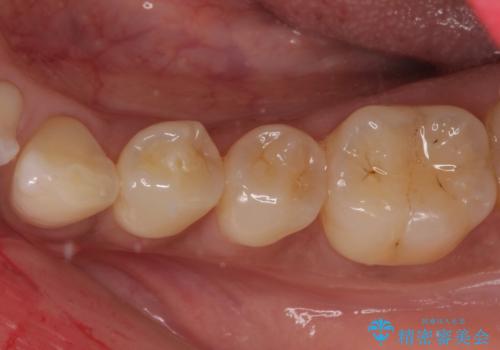

不快感の強い奥歯 オールセラミッククラウンでのむし歯治療